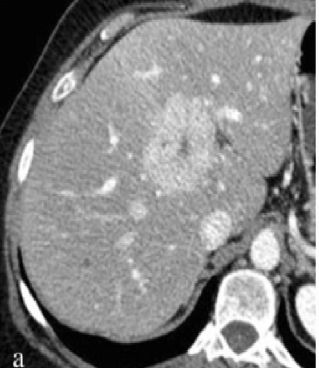

Hypervascular liver lesion with a central non-enhancing scar points to the diagnosis of _____